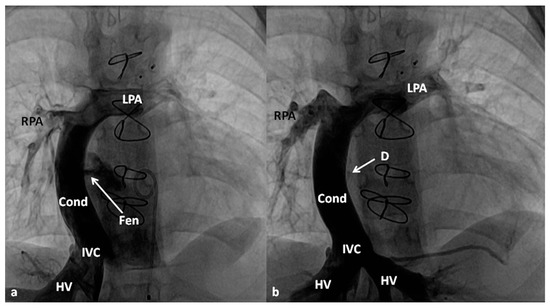

4.2.3. Stage IIIA

Between the ages of one and four years, usually one year after the bidirectional Glenn, Fontan completion is performed by redirecting the inferior vena caval flow into the PA by either a lateral tunnel [81] or an extra-cardiac non-valved conduit [76]. Extra-cardiac conduit with fenestration (Figure 10) is preferred by most surgeons. Cardiac catheterization and selective cine-angiography is usually performed prior to this surgery to evaluate pulmonary artery anatomy and pressures, trans-pulmonary gradient, pulmonary vascular resistance (PVR), and LV end-diastolic pressure to ensure their normalcy prior to proceeding with Fontan completion. Some centers use magnetic resonance imaging (MRI) for evaluation instead of angiography. During this catheterization, significant collateral vessels, if present, are trans-catheter occluded by most cardiologists.

4.2.4. Stage IIIB

The fenestration is closed by trans-catheter device implantation (Figure 11) six months to one year after stage IIIA. Occlusion of the fenestration is not necessary in all patients, although the author recommends closure to prevent arterial desaturation and paradoxical embolism.